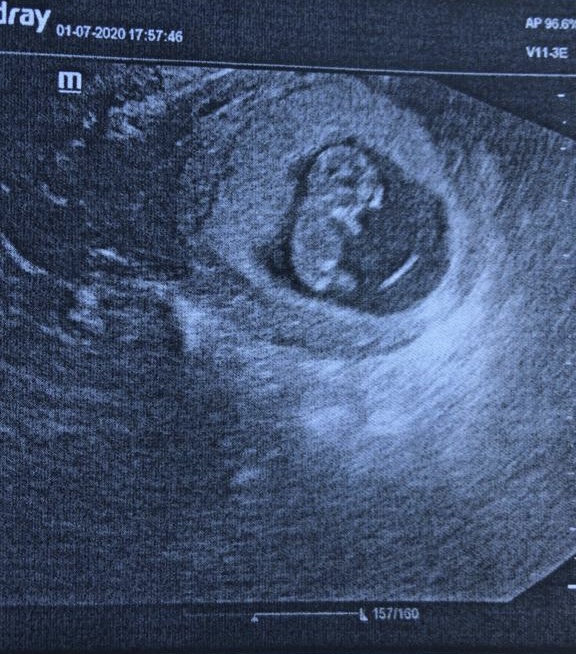

1 июля пошла на узи (без него не ставят на учёт в гинекологию, хотя моя врач была против узи до первого скрининга). Грустными глазами, кота из Шрека, я искала у мужа поддержки, а вдруг опять все повториться. Беременность подтвердилась, ребёнок развивался в срок, но матка сжималась и ее срок был на 2-3 недели меньше.